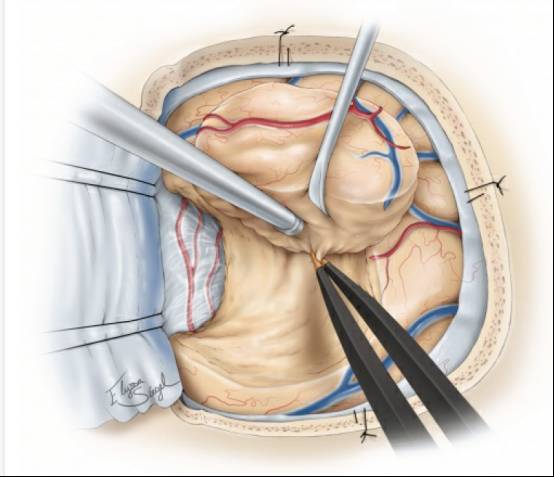

图4. 硬脑膜可采取曲线或放射状的方式打开。充分暴露肿瘤与周围正常脑皮质区域。外观相对正常的皮质常覆盖肿瘤的边缘。

在发生脑移位之前(由肿瘤内减压和/或脑脊液释放引起),笔者会根据导航,用丝线标记肿瘤的边缘。详细检查脑表面会发现,病灶累及的脑回会扩大,变色和血管减少。如果有必要,皮层电刺激可以精确定位功能区的界限。周围的大静脉和动脉要识别和保留。

图6. 首先用软脑膜下电凝痕迹标记浅表的肿瘤边缘并电凝肿瘤表面的血管。保护过路的皮质动脉和静脉。将一块肿瘤组织进行组织学检查并确认术前诊断。

图7. 笔者常常借助肿瘤组织的一致性特点和术中导航环形离断肿瘤。如果可能的话尝试整块切除肿瘤。中央部分切除会导致导航精度会大大降低。更重要的是,整块切除肿瘤能够提高手术效率,减少失血,使操作者保持沿肿瘤边缘的平面将其切除。在肿瘤的内部和外围同时操作会导致肿瘤边缘混乱不清。.